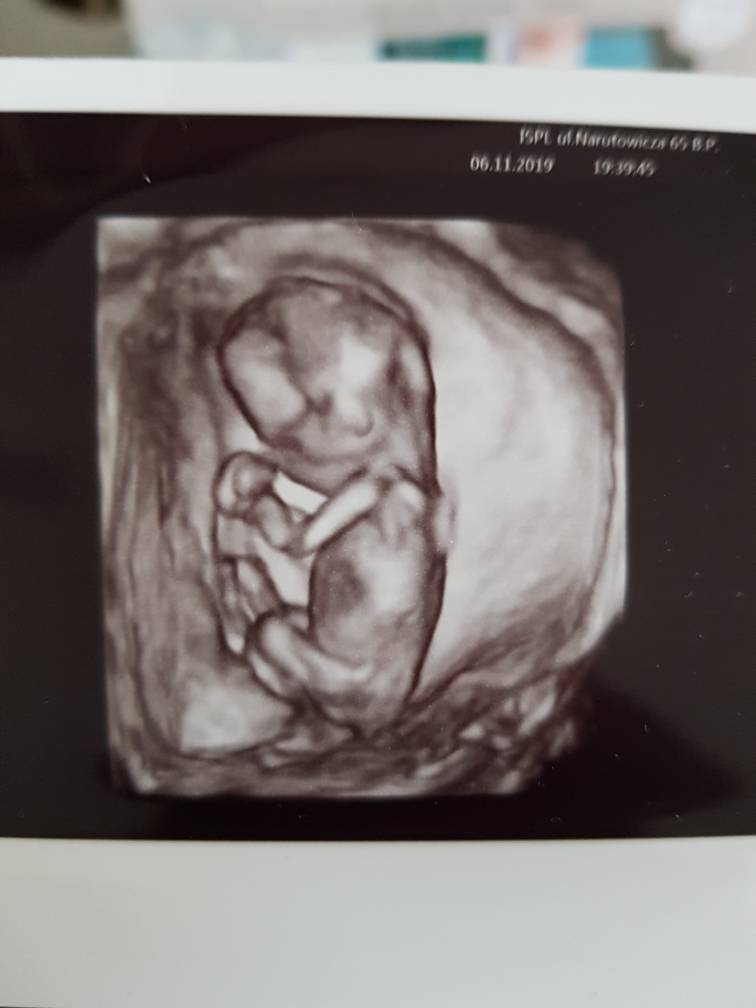

Wizyta jak pisałam bardzo udana. Przepuklina się wchłoneła, nie było już po niej śladu, ale lekarz będzie jeszcze kontrolował na kolejnym usg. Najważniejsze dziecko jest zdrowe.

Poprosiłam lekarza, żeby nie podawał płci dziecka. Tylko żeby napisał na kartce i zawinął tak, żeby nie było widać. Lekarz się śmiał, że nie wytrzymam i w drodzę podejrzę. Ale dałam radę i nie podglądałam, w domu otworzyliśmy karteczkę razem z mężem. W zdjęciach wstawiam tą karteczkę oraz zdjęcia z usg. Niestety nie dostałam zdjęcia 2d z zaznaczoną długością malucha, jedynie 3d. Z tego co pamiętam to lekarz mówił, że długość dziecka odpowiada 15 tyg., a wczoraj według om zaczęłam 16 tydzień. [emoji6]

20191107_094634.jpeg

1573117343016.jpeg

• 1573117287373.jpeg

1573117287373.jpeg

80,4 KB · Wyświetleń: 84